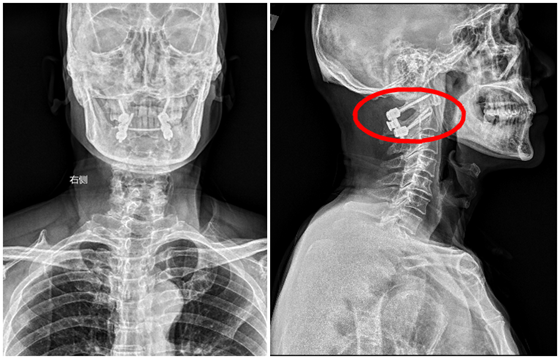

患者术后影像资料

据吴天定副教授介绍,上颈椎手术素有“脊柱外科皇冠上的明珠”之称,手术区域解剖结构复杂,毗邻延髓生命中枢,术中毫米级的偏差都可能导致严重后果。两例手术的成功实施,充分体现了湘雅常德医院医疗同质化建设的显著成效。